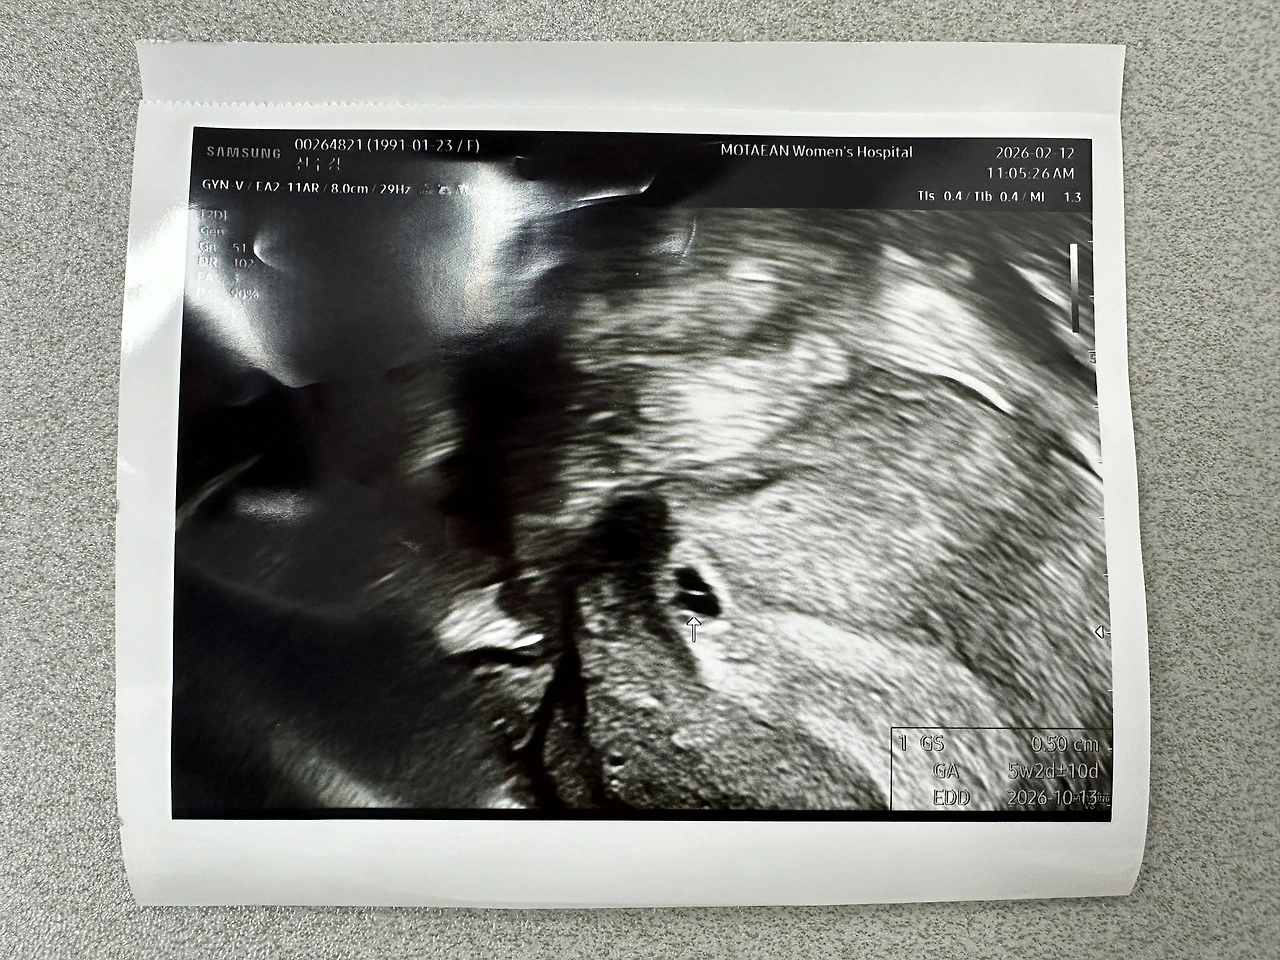

5주 2일 차 아기집과 난황

2월 12일 목요일 오전 11시 20분 예약 진료날

오늘은 수업 시작이 빨라 한 시간 먼저와 병원에서 대기를 했고 11시쯤 진료실에 들어서자마자 질초음파 준비를 마쳤다.

"이건가,, 좀 작은데 난황도 보이는 것 같고, 아기집 맞네요."

5주 2일 차 5mm의 아주 작은 아기집이었다.

"어.. 피가 좀 보이네요."

"네, 어제부터 약간씩 피가 비치더라고요. 혹시 유산기가 있는 걸까요?"

"네.. 좋은 건 아니에요. 아기집도 좀 작고 피가 보여서 장담할 수는 없겠어요."